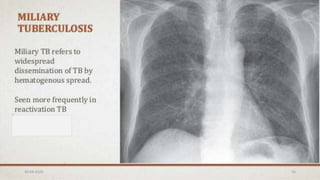

Chest X-Ray

The chest x-ray

may also appear

normal in a

patient with TB.

Findings

suggestive of TB

include upper

lobe infiltrations,

cavitary

infiltrates and

lymph node

involvement.

Chest X-Ray The chestx-ray may also appear normal in a patient with TB. Findings suggestive of TB include upper lobe infiltrations, cavitary infiltrates and lymph node involvement. 30-04-2020 32